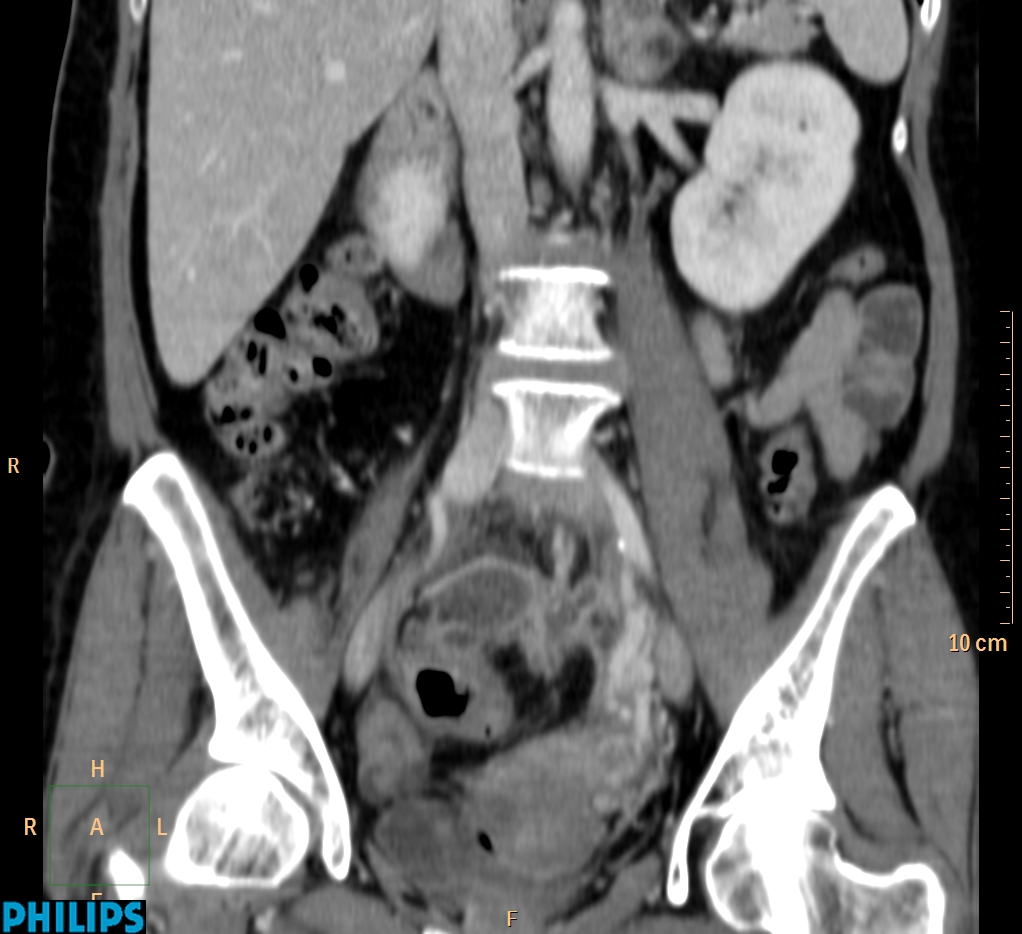

ΕΚΚΟΛΠΩΜΑΤΑ ΠΑΧΕΟΣ ΕΝΤΕΡΟΥ Posted by ΙΠΠΟΚΡΑΤΕΙΟ ΙΩΑΝΝΙΝΩΝ | Dec 16, 2020 | ΠΕΠΤΙΚΟ | 0 ΚΛΙΝΙΚΑ ΣΤΟΙΧΕΙΑ – ΙΣΤΟΡΙΚΟ υποτροπιάζοντες επαναλαμβανόμενοι πυρετοί κυρίως απογευματινές ώρες ΕΡΓΑΣΤΗΡΙΑΚΟΣ ΕΛΕΓΧΟΣ ΑΠΕΙΚΟΝΙΣΤΙΚΟΣ ΕΛΕΓΧΟΣ διακρίνονται τα αποστήματα στην ελάσσονα πύελο, καθώς και εκκολπώματα με εικόνα πάχυνσης του τοιχώματος του σιγμοειδούς ΣΥΖΗΤΗΣΗ